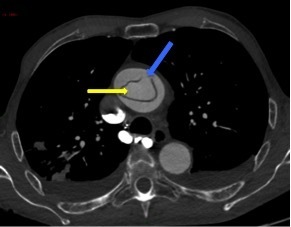

Un angioscanner thoraco-abdomino-pelvien est donc réalisé. Les Figures 11, 12, 13, 14 et 15 présentent des reformations axiales issues de celui-ci.

Question 7 : Concernant les structures légendées, quelles sont la/les proposition(s) exacte(s) ?

Vrai chenal

Déchirure intimale, qui constitue la porte d’entrée de la dissection.

Artère carotide commune droite

Artère coronaire droite naissant du sinus de Vasalva

Visualisation de la déchirure intimale d’où nait le faux chenal, dans lequel la déchirure est éversée, au niveau de l’aorte ascendante, avec un flap intimal étendu au tronc artériel brachio-céphalique, à la carotide commune droite et à la carotide commune gauche. En revanche absence d’extension au sinus de Vasalva, à la coronaire droite.

Dissection aortique de type A selon Stanford avec porte d’entrée de l’aorte ascendante en amont du tronc artériel brachio-céphalique et extension aux troncs artériels supra-aortiques. Pas d’extension au sinus de Vasalva, aux coronaires ni à l’aorte descendante. Pas de signe de rupture intra-péricardique ou intra-médiastinale.

La présence d’un flap intimal est pathognomique de la dissection aortique.